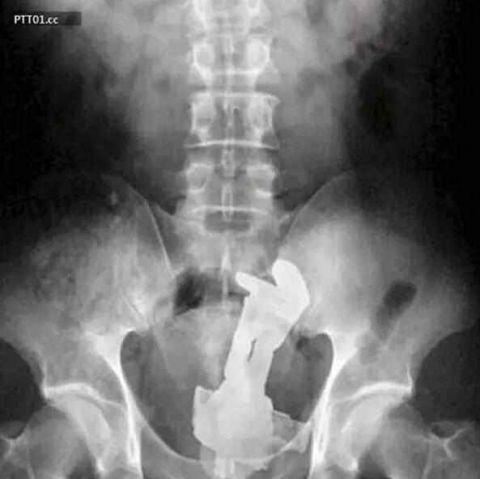

手机也可以塞进去